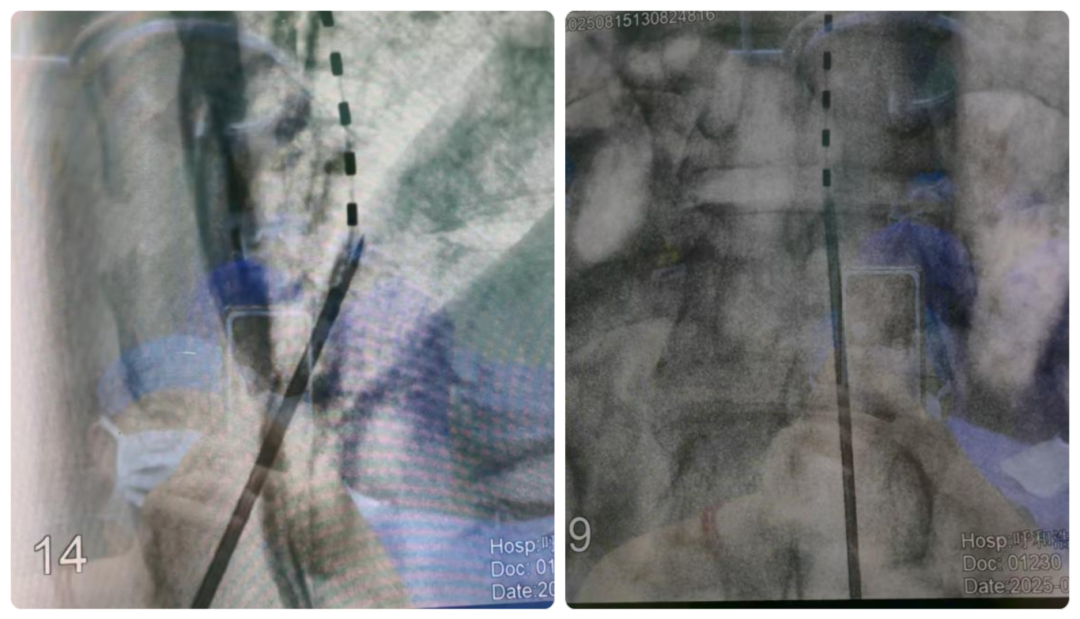

2025年8月,疼痛科完成我院首例脊髓电刺激手术。此次手术邀请首都医科大学宣武医院神经外科倪兵主任,我院神经外科、麻醉科、骨脊柱科协助完成,突破技术壁垒,为慢性难治性疼痛患者找到新的治疗方法!

脊髓电刺激技术被称为慢性顽固性疼痛治疗的“终极武器”之一,是难治性疼痛的“电子特效药”,其原理是通过微创方式将电极植入椎管内,以微弱电流干扰疼痛信号向大脑的传递,从根源上缓解甚至消除疼痛。该技术对操作精度要求极高,需精准定位电极位置、调控刺激参数,既要有效覆盖疼痛区域,又要避免对正常神经功能造成影响。

此次接受治疗的患者,因脊髓损伤常年遭受下腹胀痛及下肢麻木、痉挛性疼痛等症状困扰,药物治疗效果递减,生活质量严重下降。测试电极植入后,在倪兵主任的指导下,全程调整参数,以期症状缓解。